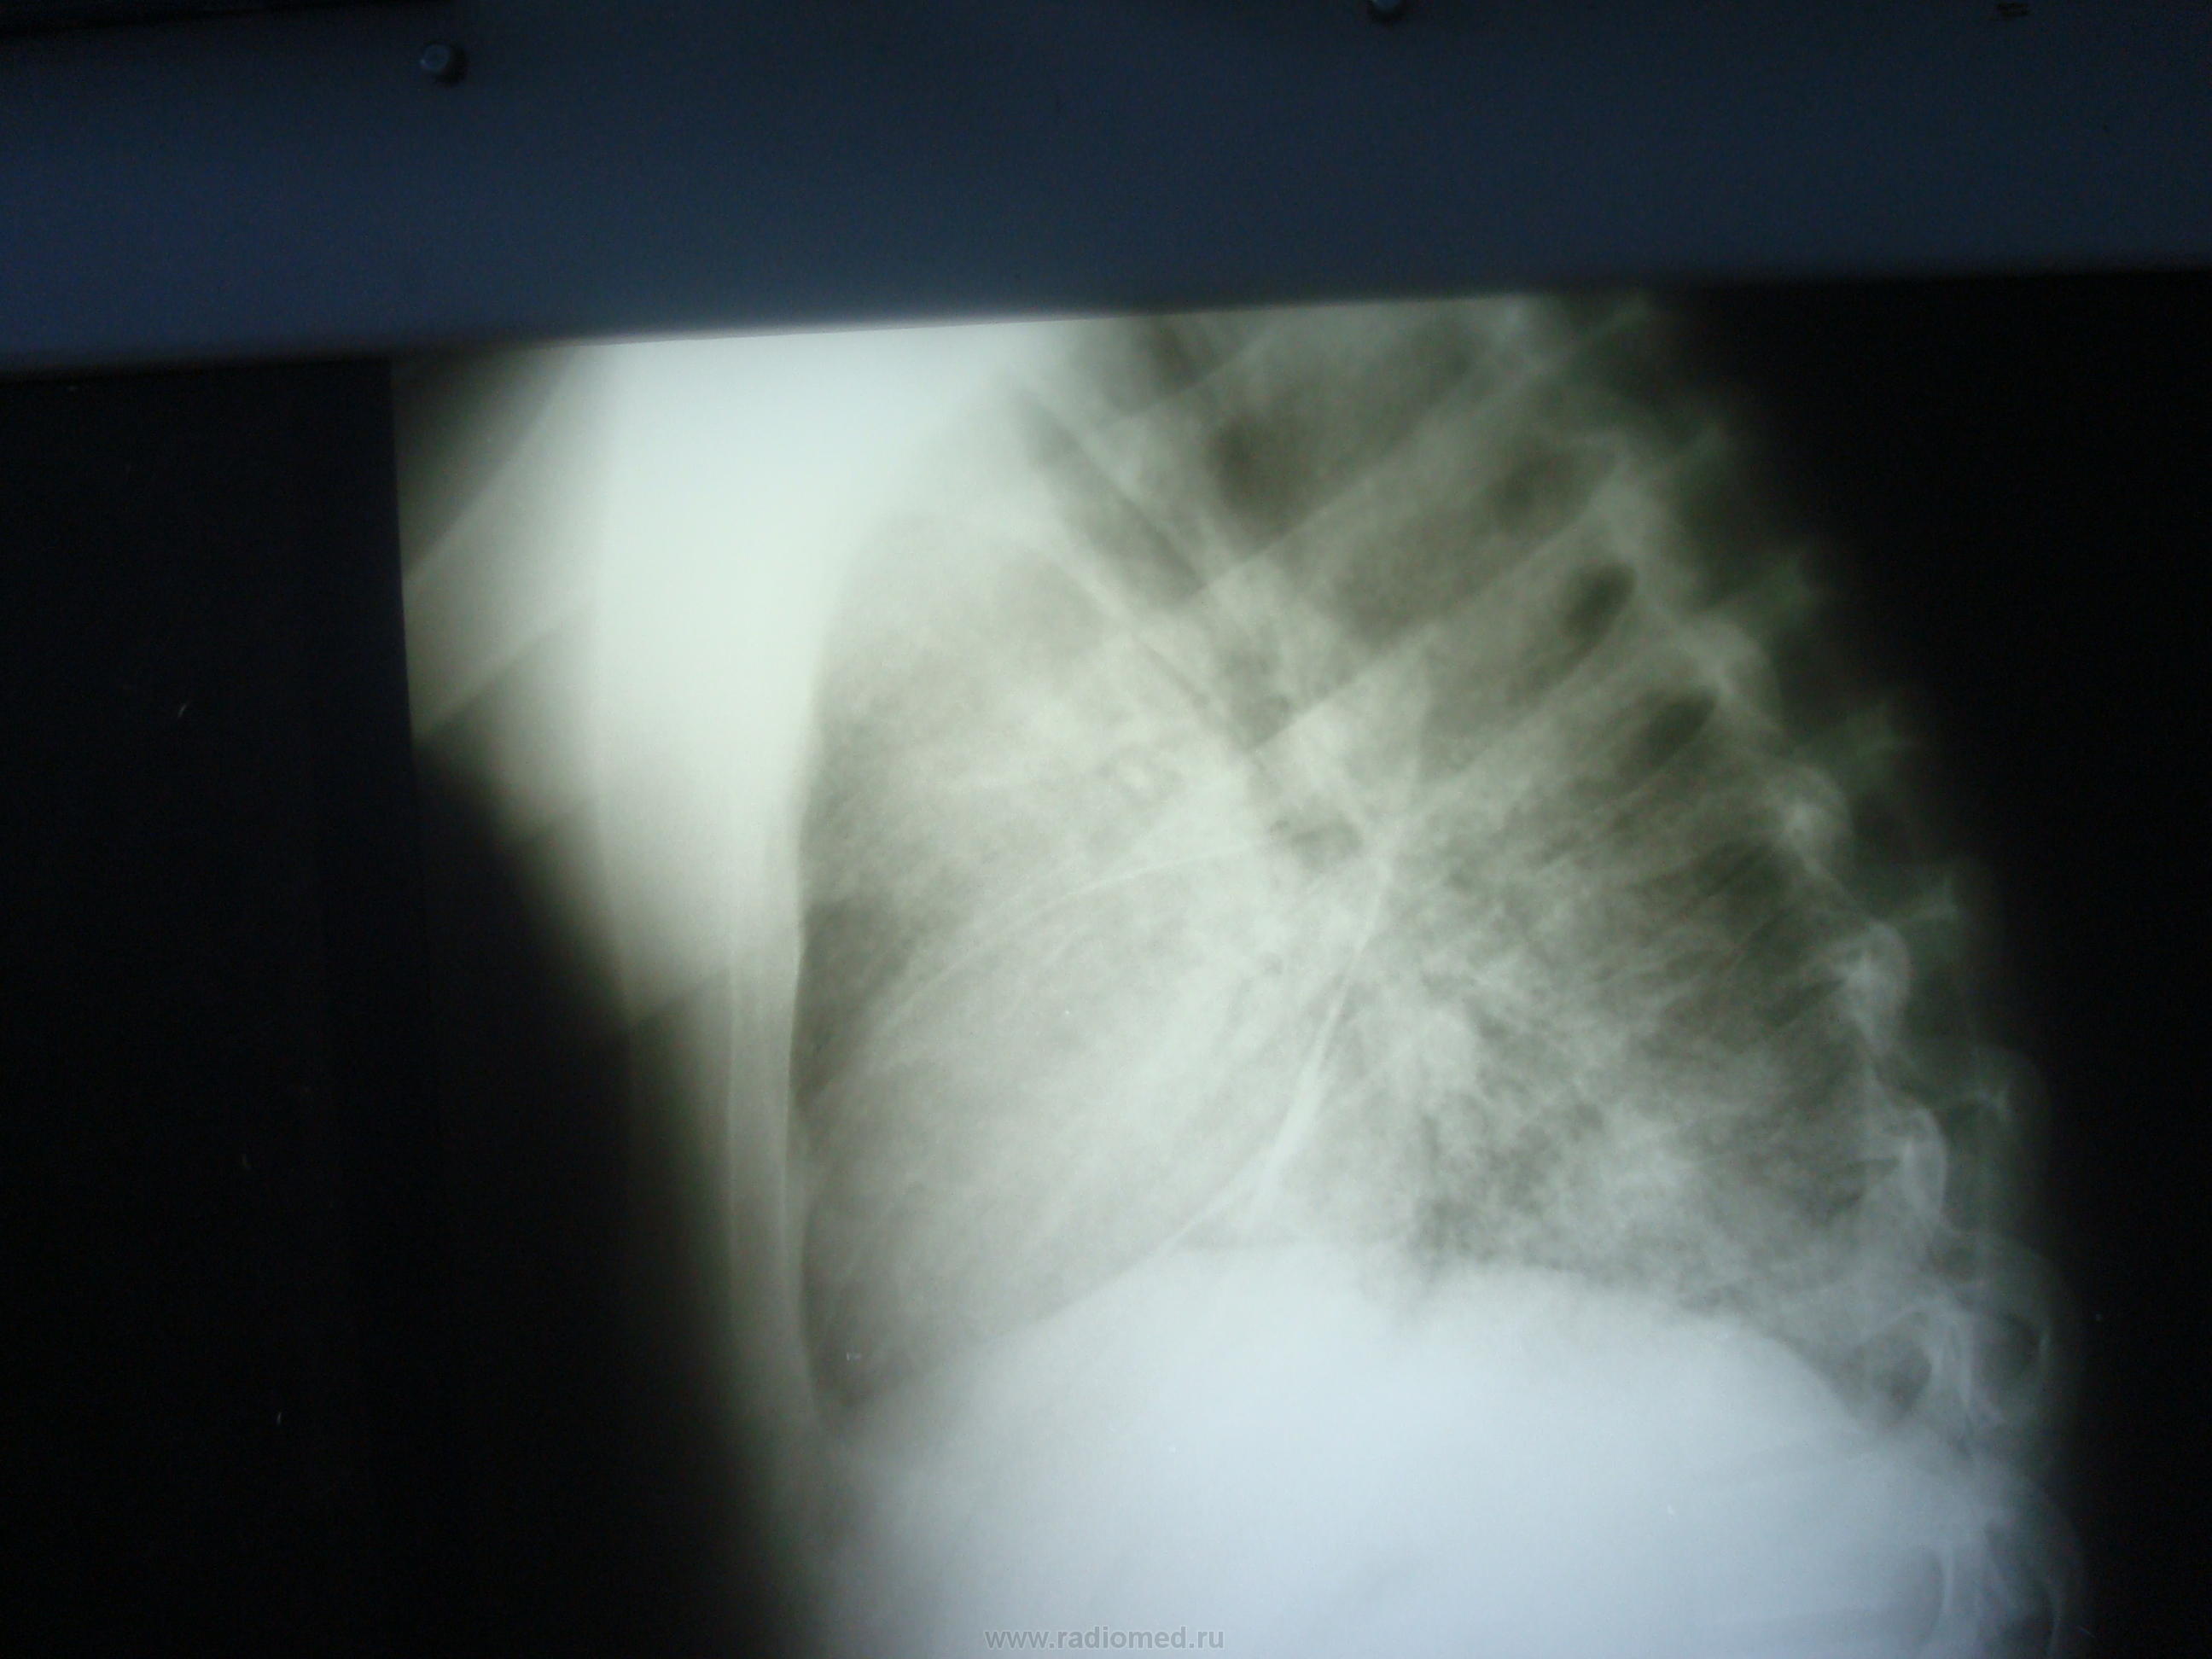

Пациент 21 год.Находился на лечении в гематолгическом отделении. DS Острый лейкоз.При поступлении в отделение 22..07.2013г выполенена R-грамма лёгких в прямой проекции.С 24.07.2013г появилсь лихорадка 38-39 градусов. 27.07 .2013года была выполена контрольная R-графия лёгких в 2-х проекциях. Состояние ухудшалось, появилась одышка 28.07.2013г. контрольная R-графия лёгких. Как можно расценить найденные в лёгих изменения?

связанная с лейкозом. Очаги и фокусы в легких определяются с обеих сторон в средних и нижних отделах с реакцией междолевой плевры.  Лечить основное заболевание и пневмонию. Не исключаю и лекарственное поражение легочной ткани.

Пульмонологи на момент 27.07.2013г., в нижнем поле  слева выслушивали влажные хрипы,  которы были расценены, как проявление пневмонии.

2сторонняя пневмония.

Двустороннее усиление легочного рисунка за счет интерстициального компонента, мелкие очаги. Не исключено, что это лейкемоидные инфильтраты, особенно если бластов много в анализе крови